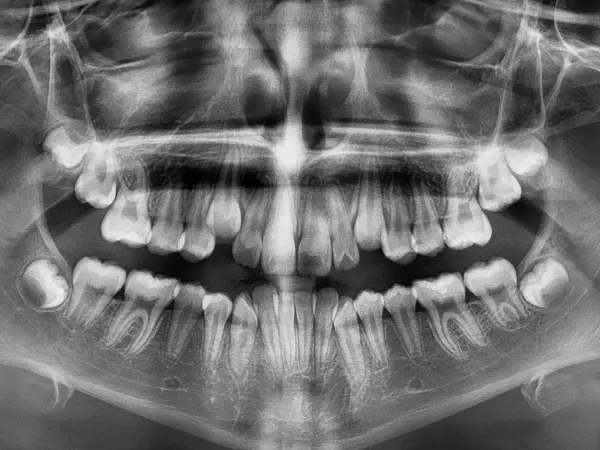

Dental crowding is a type of malocclusion – or “bad bite” – that occurs as a result of this problem. Rather than grow into their correct positions, when the teeth do not have enough room, they will grow in unnatural positions, trying to find a space to grow in competition with other teeth. This can lead to crooked, crowded teeth that don't line up properly.

Dental crowding is a common problem where teeth are not aligned right. This can be because of genetics or other factors. When this happens, teeth fight for space and end up crooked.

Whatever the cause of crowding, there is a wide spectrum of different severities of crowding. Some causes may result in only one twisted tooth; others may cause the entire row of teeth to grow in improperly.